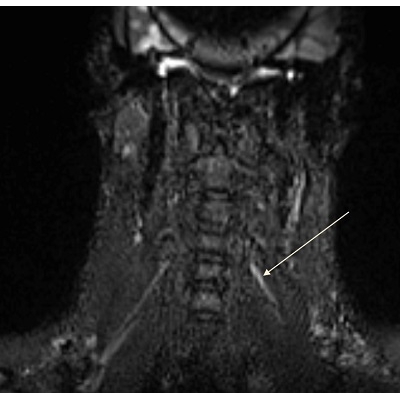

| Football Player Gets Burned After Thinking He Only Had A Burner - Page #3 | |||